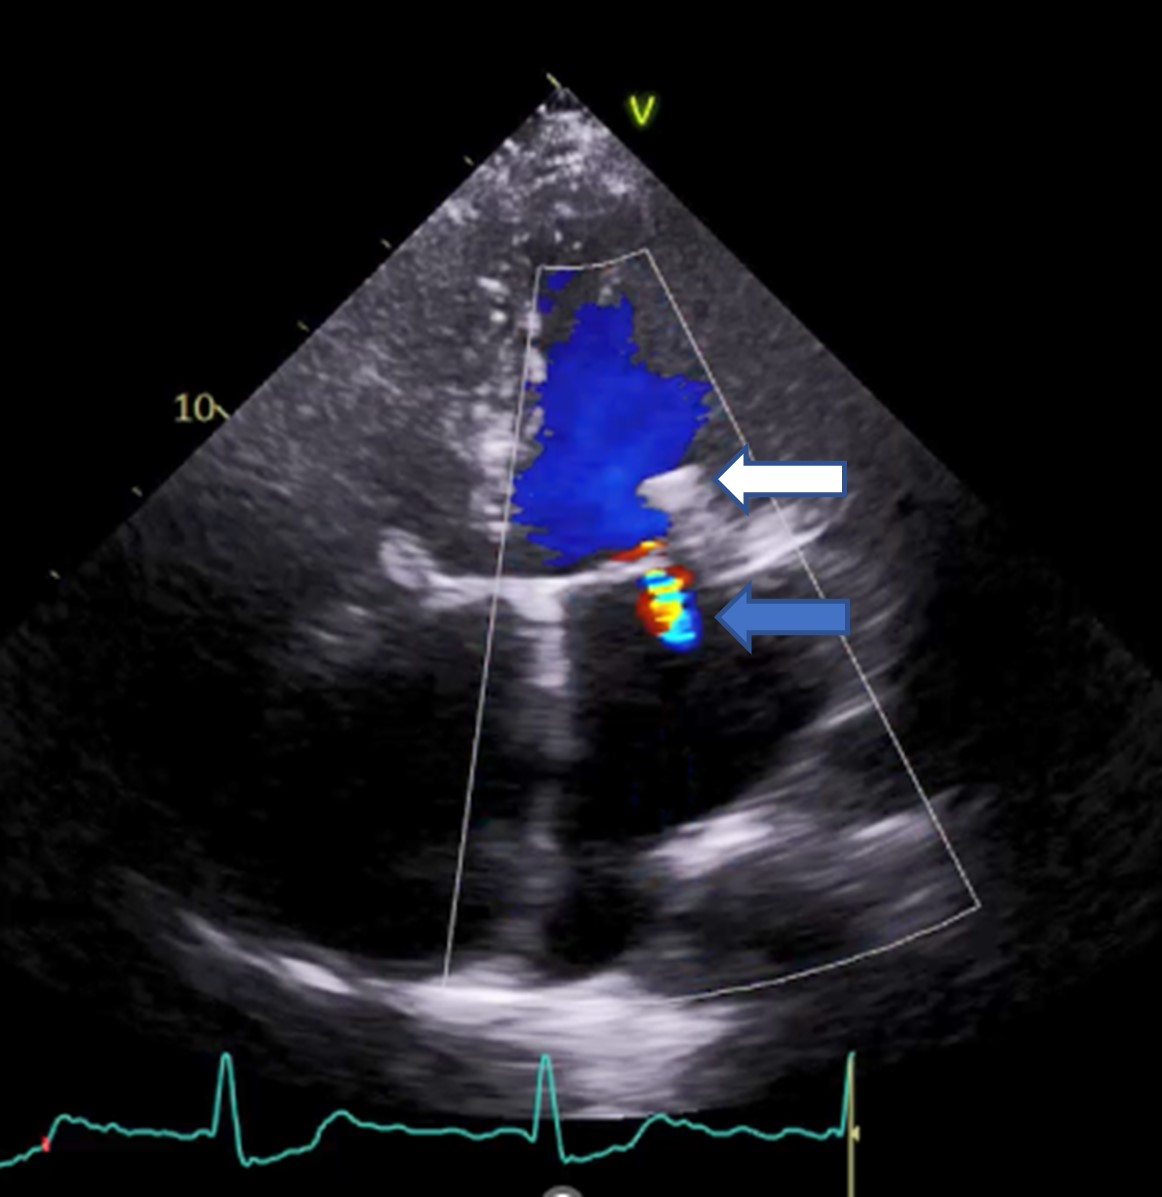

Zabieg operacyjny wady wykonuje się najczęściej w dzieciństwie. W przypadku wad złożonych bywa on często wieloetapowy. W wieku dorosłym pojawiają się natomiast odlegle powikłania wady czy następstwa odległe samej operacji. Tacy pacjenci po okresie stabilnego samopoczucia mogą wymagać kolejnych zabiegów. W ostatnich latach wzrosła liczba kardiologicznych interwencji przezskórnych, które coraz częściej wykonuje się również u chorych z wadami wrodzonymi. Ugruntowaną pozycję ma już przezcewnikowa implantacja zastawki tętnicy płucnej, raportowane są pojedyncze przypadki przezcewnikowej implantacji zastawki aortalnej, a w ostatnich 2-3 latach także zabiegi przezskórnej naprawy zastawek przedsionkowo-komorowych metodą brzeg-do-brzegu poprzez zbliżenie płatków zastawki za pomocą implantowanych klipsów (Rycina 1).

Rycina 1. Istotna redukcja fali zwrotnej mitralnej (strzałka niebieska) za pomocą systemu Pascal (strzałka biała) u pacjenta z tetralogią Fallota w odległym czasie po pierwotnej korekcji wady. Przezklatkowe badanie echokardiograficzne, projekcja koniuszkowa czterojamowa.